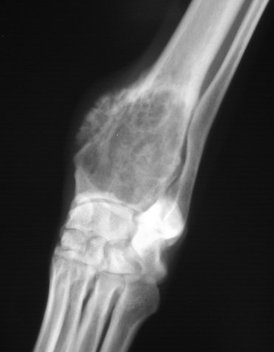

Primary Bone tumor

usually found in the metaphyseal region of long bones

ex. osteosarcoma